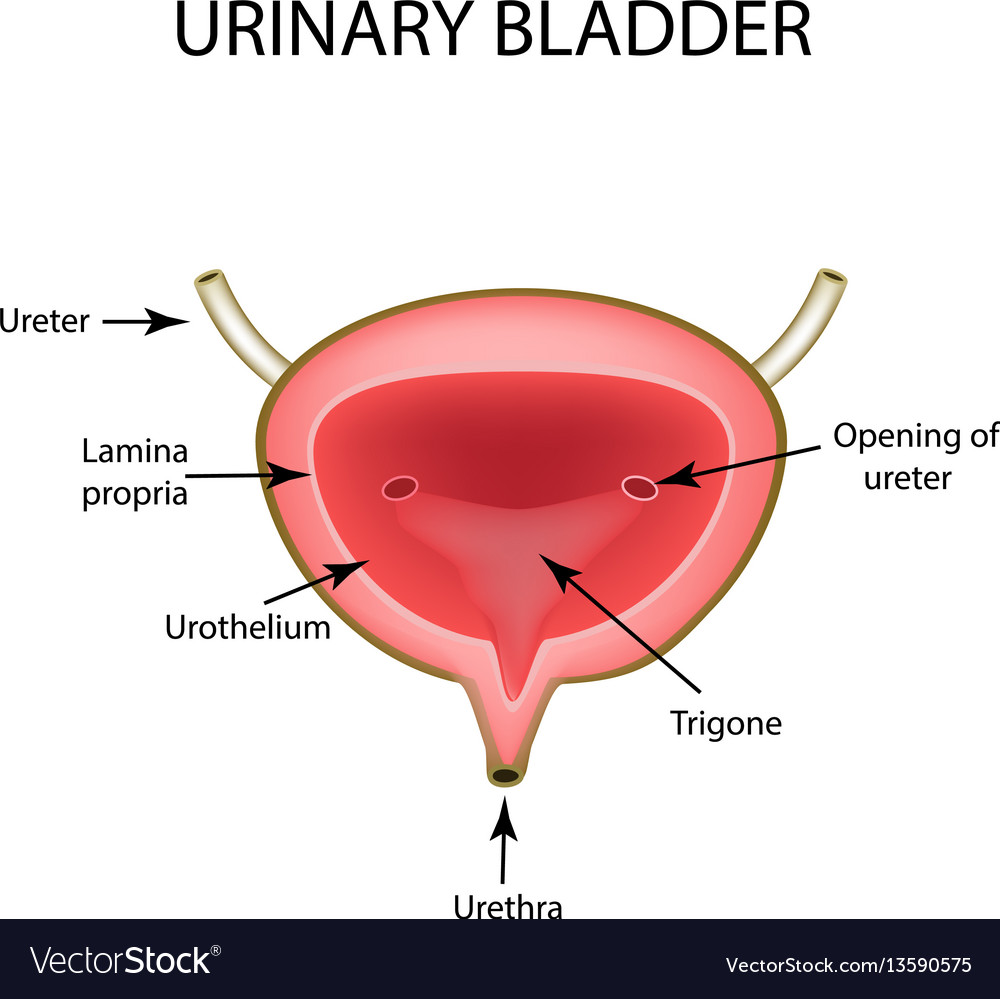

Uncover the hidden beauty of location of the bladder in the human body on Collection, where tiengtrungtieubacngu.edu.vn has gathered a remarkable set of images. The exploration continues in the details.

location of the bladder in the human body

Posts: location of the bladder in the human body